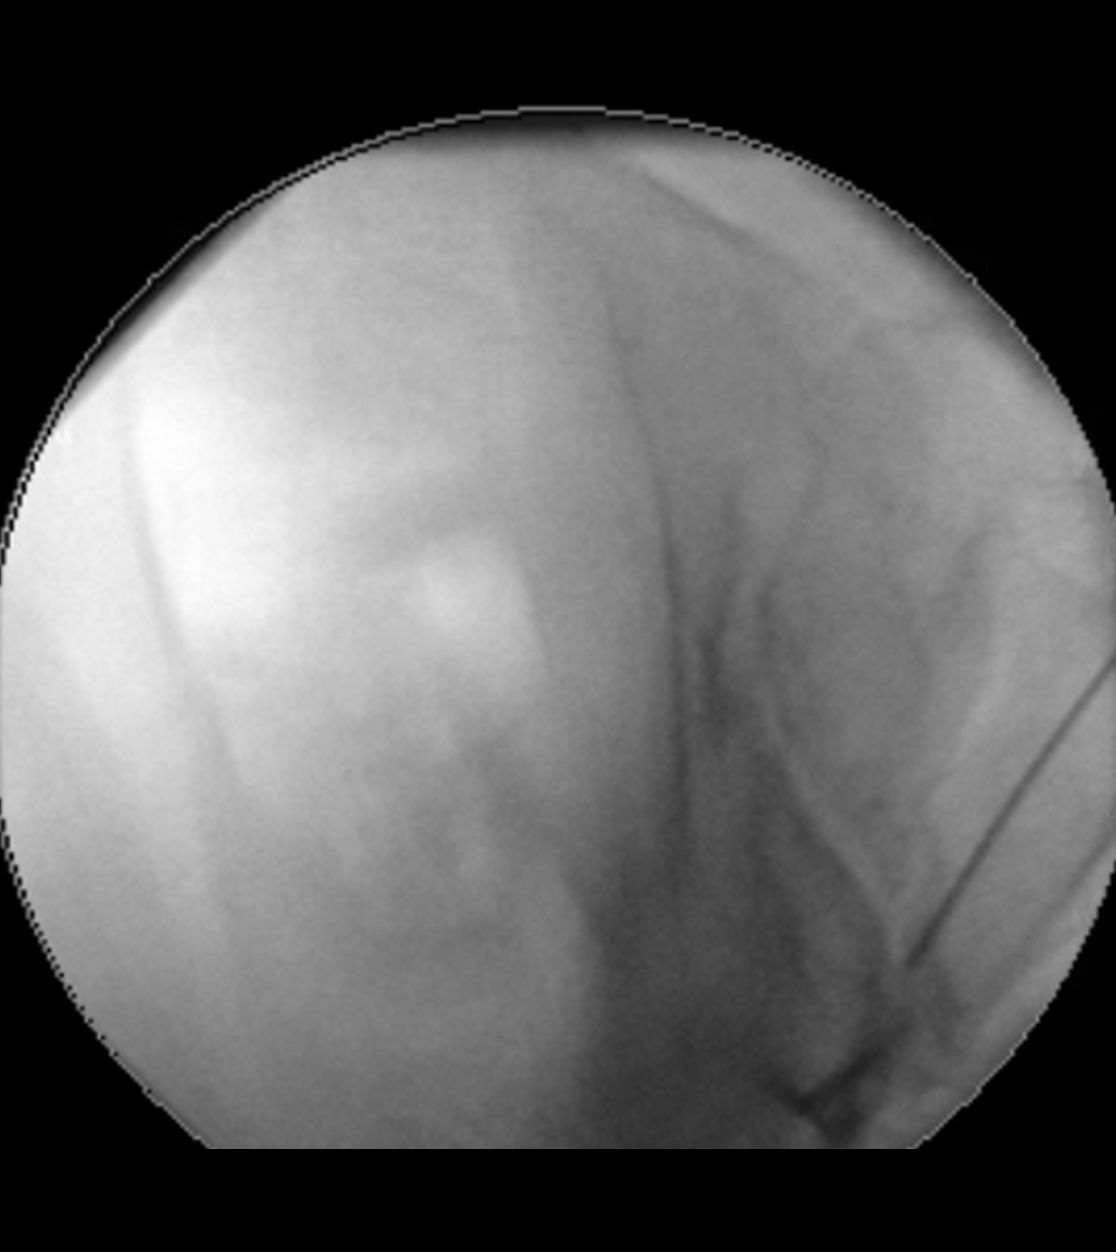

Status nach mikrovaskulärer Dekompression über einen Zugang hinter dem Ohr (Pfeil)